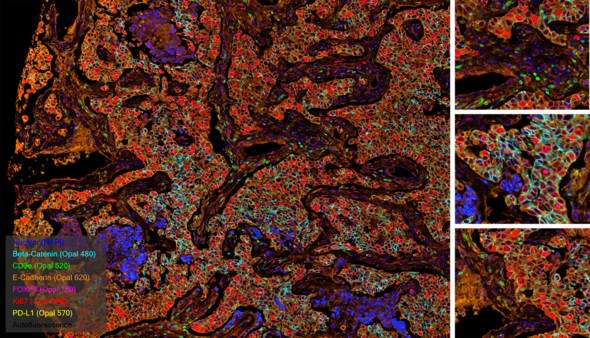

Cyclic immunofluorescence (cyclic IF or CyCIF1 and originally referred to as MxIF2) is a high-plex imaging technique. Multiple fluorophore-conjugated antibodies are added to the slide in each round of staining. After each round of imaging, the fluorescent dyes are inactivated by chemical inactivation, photobleaching, or detergent-based stripping so that the same fluorophores can be used in subsequent rounds.2 By using the same fluorophores in multiple rounds of staining, cyclic IF minimizes the need for the use of uncommon fluorophores and extensive optimization.

This iterative process can be performed multiple times, allowing for the detection of multiple antigens in the same tissue sample. The images acquired after each round of staining are all merged prior to being analyzed, using nuclear staining as an alignment guide.

At Fortis, we use sequential immunofluorescence (seqIF™) on the Lunaphore COMET™. It involves successive cycles of staining-imaging-elution, without any human intervention. COMET™ uniquely preserves sample morphology and epitope integrity by efficiently removing antibodies and residues from the sample. This enables samples to be reused downstream for other applications like H&E, IHC, spatial transcriptomics, or sequencing.